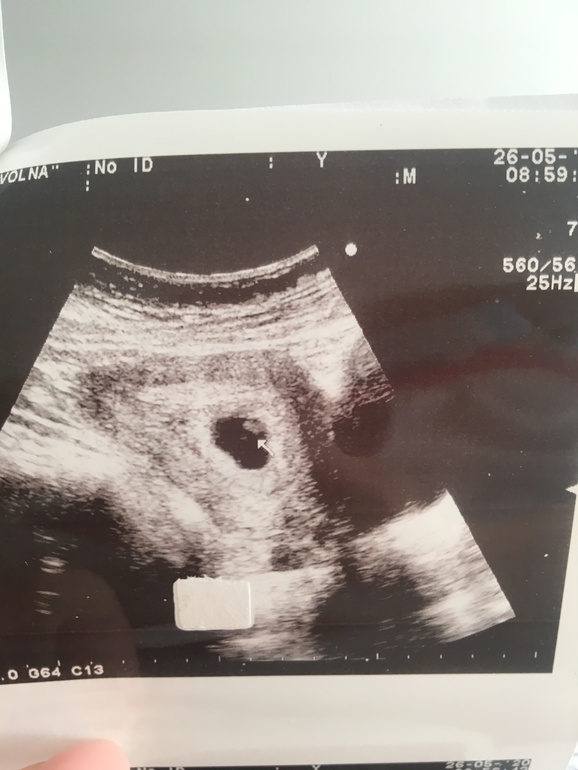

Первое УЗИ

Растите здоровенькими!) Я тоже платно хожу, и узиста вроде советуют, но почему она наотрез отказалась смотреть внутри и мерять КТР - не знаю( На фото вроде хорошо видно, что кто-то живет там)

Просто до этого 2 ЗБ были, но там всегда смотрели внутри, не знаю, почему в этот раз отказали( Беспокоит просто, что КТР не мерили, и пульсация эта вместо сердцебиения)